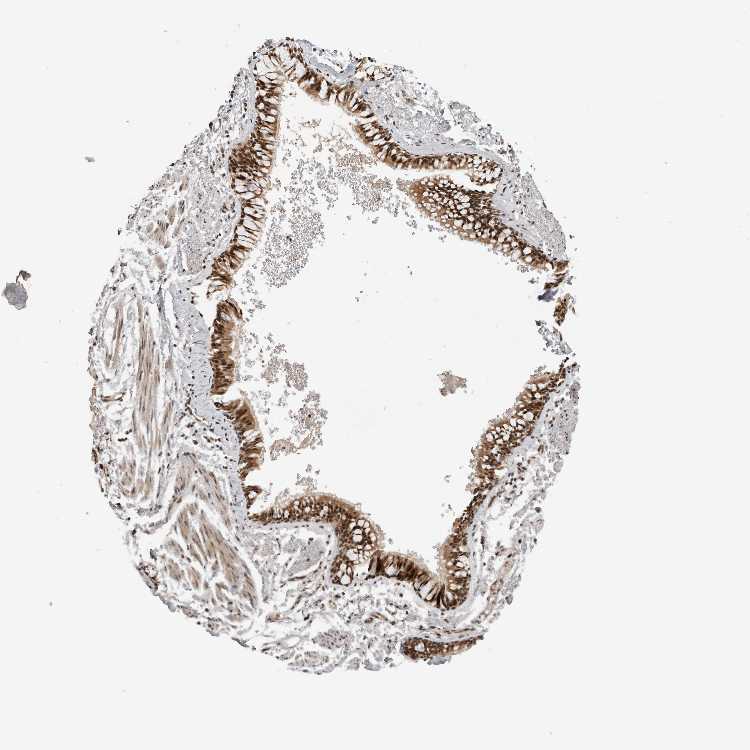

SOFT TISSUE 1 - Antibody stainingi

Antibody staining in the annotated cell types in the current human tissue is reported as not detected, low, medium, or high, based on conventional immunohistochemistry profiling in selected tissues. This score is based on the combination of the staining intensity and fraction of stained cells.

Each image is clickable and will lead to virtual microscopy that enables deeper exploration of all samples and also displays staining intensity scores, fraction scores and subcellular localization as well as patient and tissue information for each sample.

Antibody HPA024238

Fibroblasts High

SOFT TISSUE 2 - Antibody stainingi

Peripheral nerve Medium